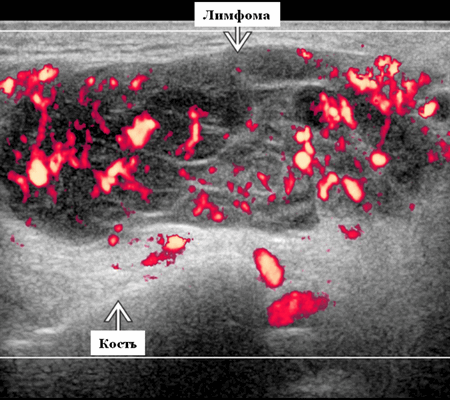

Цветной допплер. Узловая НХЛ. Выраженная центральная или внутриузловая гиперваскуляризация. Паренхима при неходжкинской лимфоме более диффузная железистая гиперваскуляризация. Васкуляризация от умеренной до выраженной в плохо очерченных образованиях.

- Цветной допплер. Узлы щитовидной железы: неспецифические, гиповаскулярные или имеют хаотические интранодулярные сосуды. Центральные области более васкулярны, чем периферические.

- Цветной допплер: смешанная васкуляризация с выраженным сосудистым рисунком и наличием периферической васкуляризации. Периферическая сосудистая сеть редко встречается в узлах НХЛ

Цветовой допплер: смешанная сосудистая сеть с выраженными внутриузловыми сосудами и наличием периферической сосудистой системы. Одна только периферическая сосудистая сеть редко встречается в узлах НХЛ. Спектральный допплер: переменное интранодальное внутрисосудистое сопротивление, которое носит неспецифический характер.